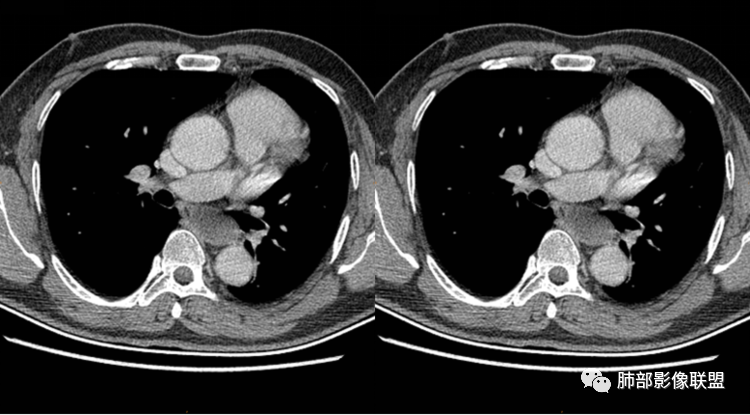

患者,男,43岁,无意间发现纵隔肿物,无胸闷胸痛,无心慌气短,无咳嗽,无吞咽困难等不适。体检发现的,无症状。

气管、左主支气管后方,食道左侧囊性占位,壁薄且均匀、光滑。气管及左主支气管受压凹陷、变形。

食道也受压变形、移位。